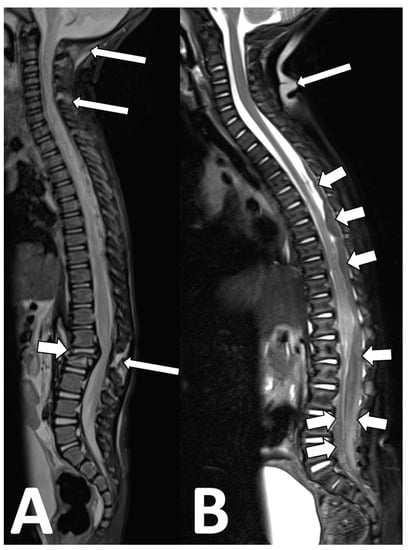

Our contextualized MRI non-accidental trauma protocol includes sagittal T2-weighted images with fat suppression to assess for the presence of ligamentous injury, intraspinal pathology, and any bone edema (Figure 9).

Figure 9. Non-accidental trauma spine imaging. (A) A 23-month-old male with suspected non-accidental trauma. The fat-suppressed sagittal T2 images show an L2 vertebral fracture with mass effect on the conus ((A), short arrow), as well as multiple levels of interspinous ligament injury at C1–6 and at L2–3 ((A), long arrows). Of note, using an inversion recover (STIR) technique for fat suppression in this case limits the evaluation of the spinal cord and spinal canal. (B) An 8-month-old male with suspected non-accidental trauma. Here, a fat-saturation technique was used, which improves the visibility of the spinal cord and identification of large intradural hematomas compressing the cauda equina ((B), short arrows). A downside of fat saturation is the inhomogeneity of the fat suppression, with areas of failed fat suppression ((B), long arrow).